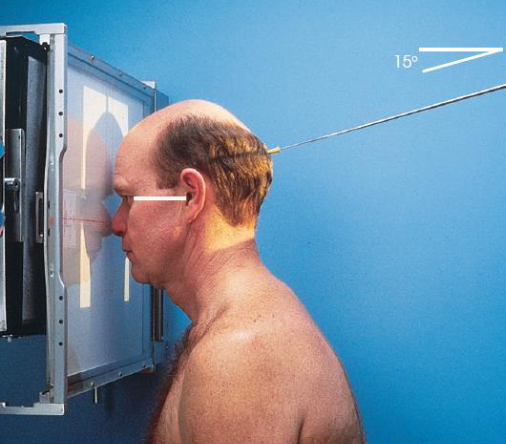

PA/PA axial (Caldwell) skull

patient position:

seated upright or prone

MSP centered to midline

forehead and nose resting on Bucky

part position:

MSP and OML perpendicular to IR

respiration suspended

CR:

PA: perpendicular to IR, exiting nasion

PA axial: 15 degrees caudad, exiting nasion

collimation:

1 inch beyond skin line of the skull